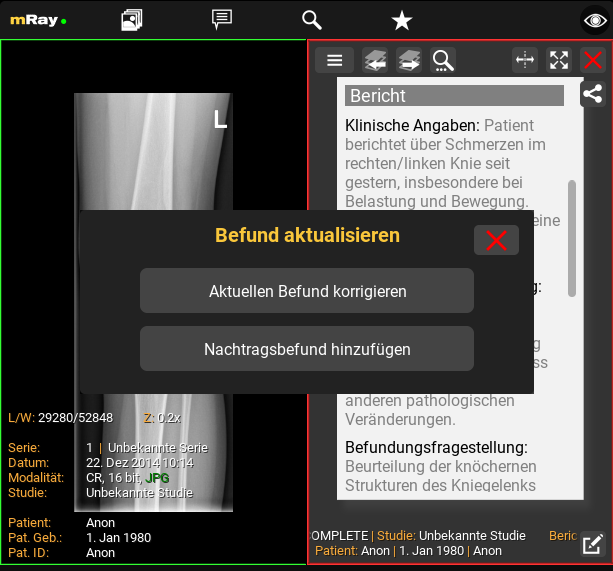

12.6. Korrekturbefund und Nachtragsbefund

Freigegebene Befunde können nicht verändert werden, jedoch ist es möglich, einen Korrektur- oder Nachtragsbefund zu erstellen. Diese sind versioniert, sodass die ursprüngliche Version des freigegebenen Befunds weiterhin einsehbar bleibt.

Um einen Korrektur- oder Nachtragsbefund zu erstellen, klicken Sie auf denselben Button wie zur Befundbearbeitung. Vorab werden Sie gefragt, welche Art von Befund Sie erzeugen möchten.

12.6.1. Korrekturbefund

Ein Korrekturbefund erlaubt die vollstandige Überarbeitung des bereits freigegebenen Befundtexts.

12.6.2. Nachtragsbefund

Ein Nachtragsbefund ermöglicht es einmalig einem bestehenden Befund weitere Informationen hinzuzufügen. Der bestehende Befundtext ist nicht editierbar.